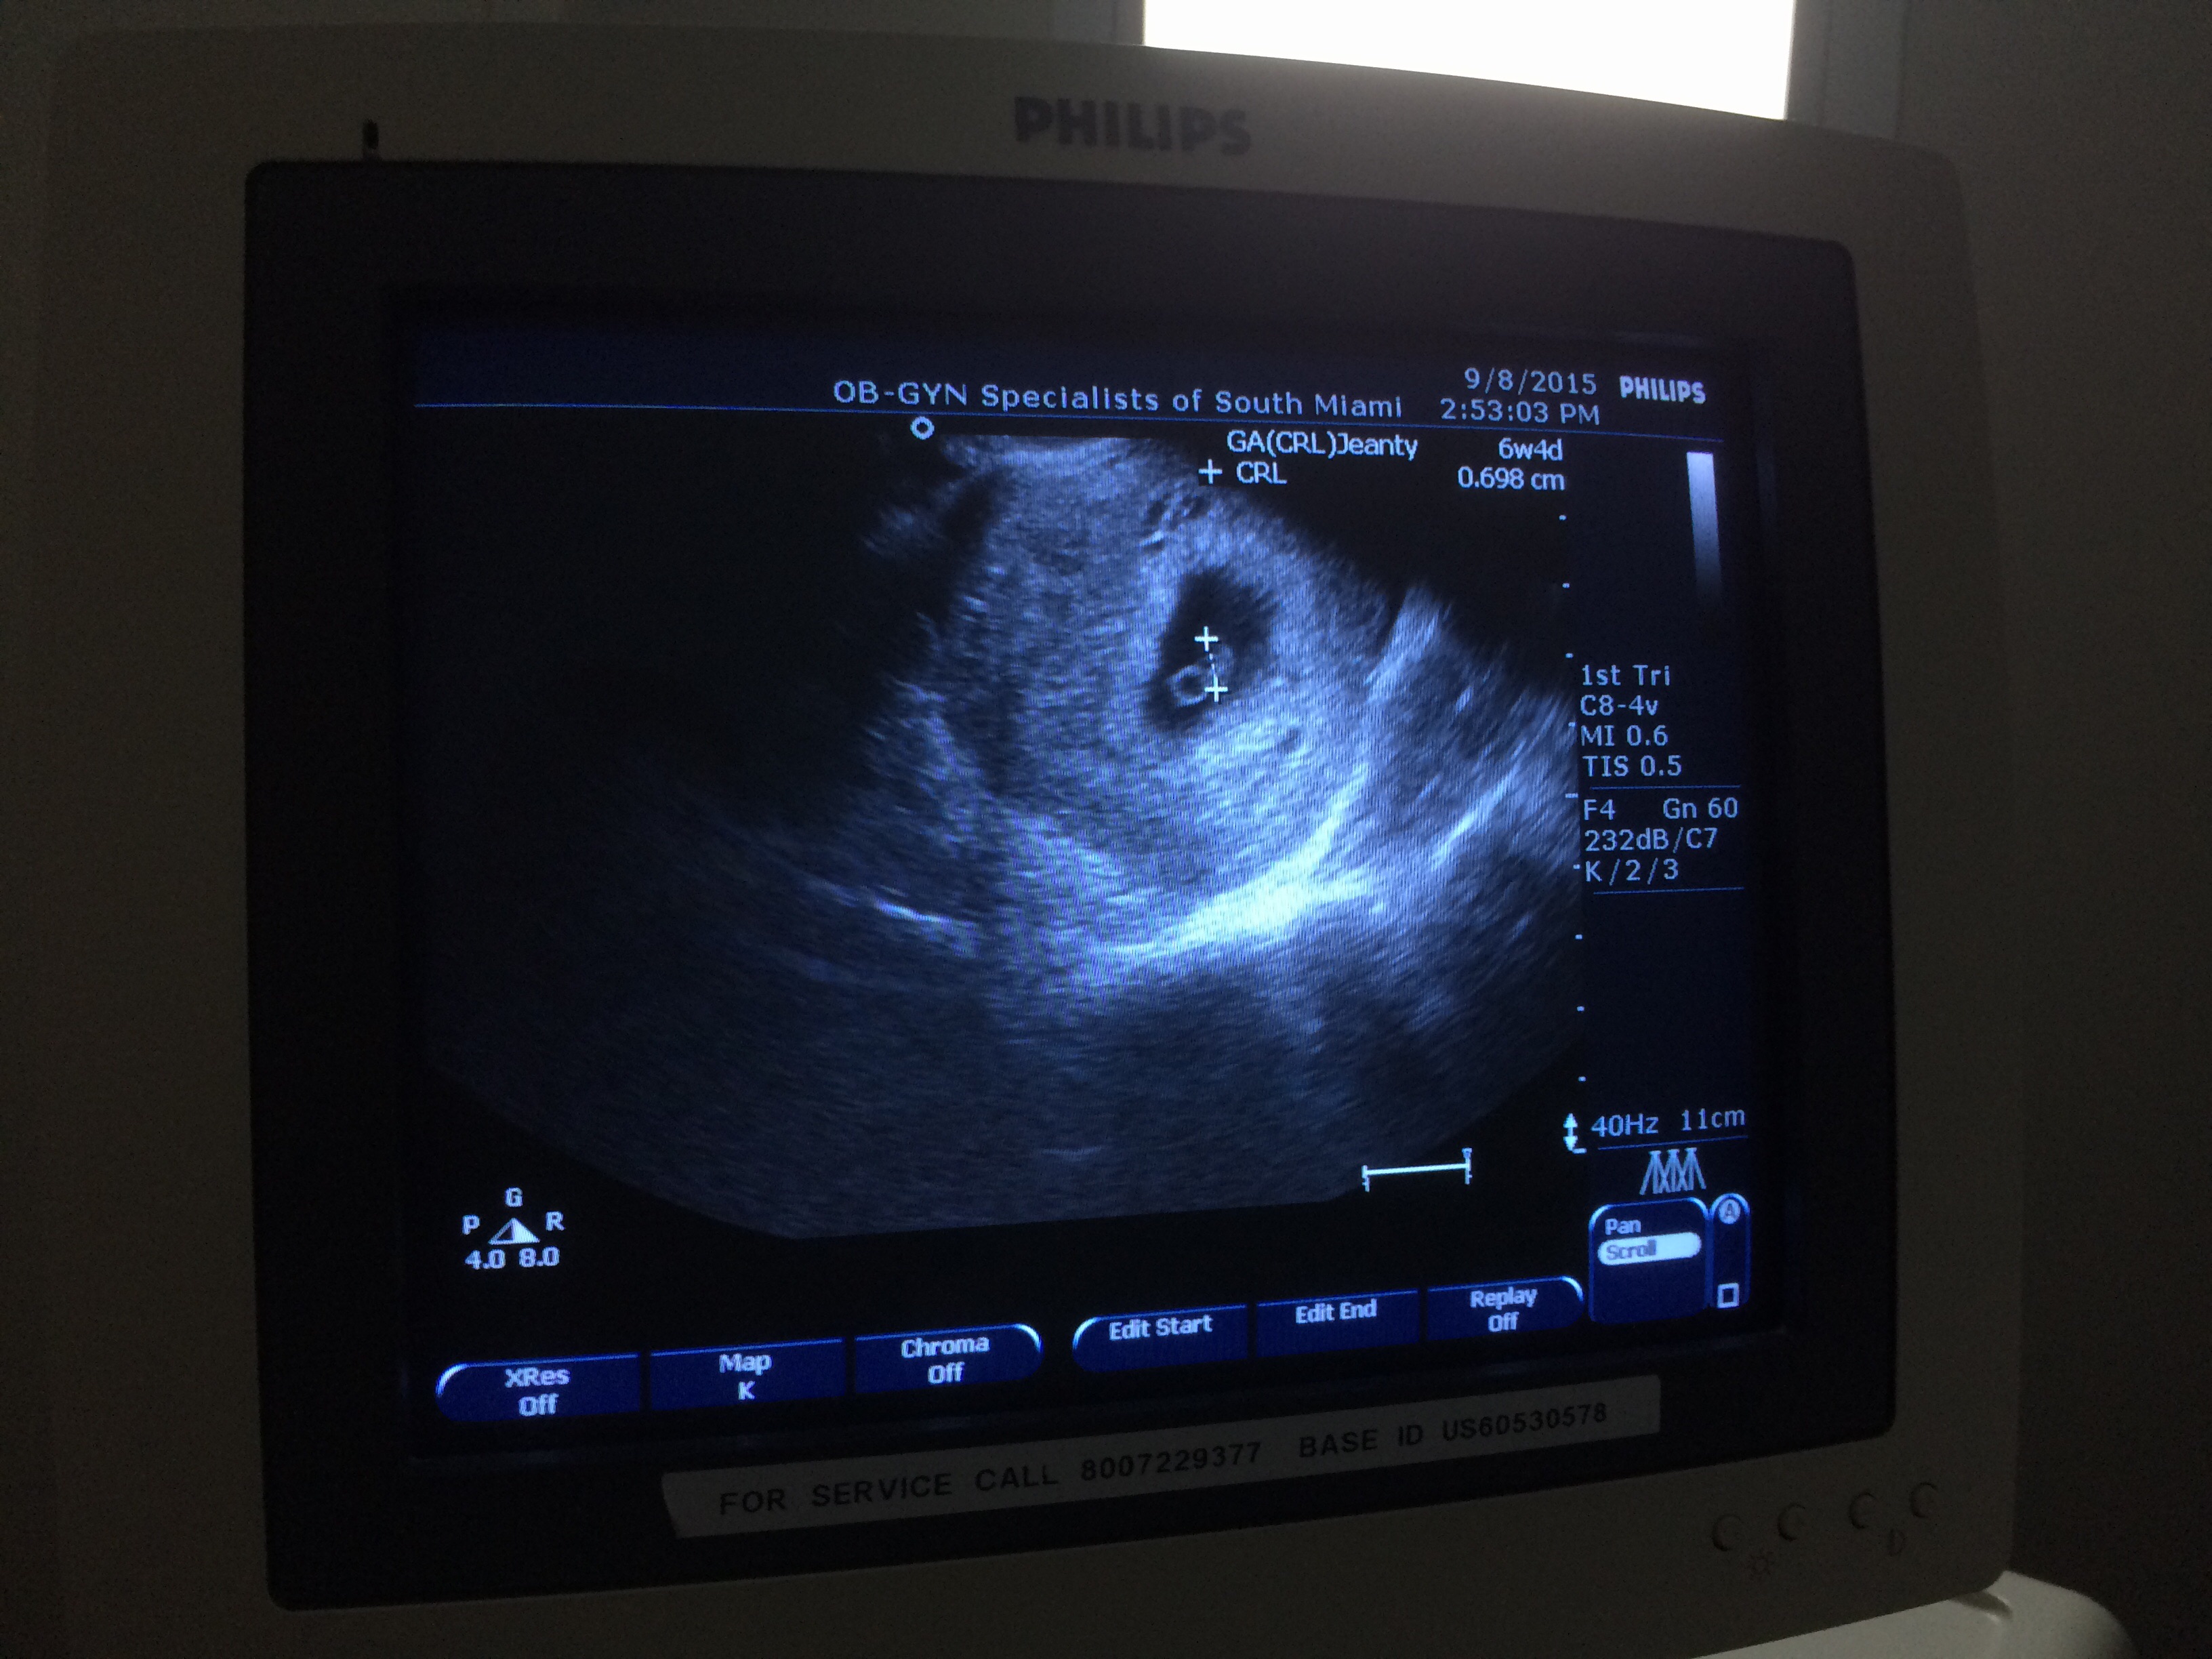

• First ultrasound today, measuring 6wks 4days just as we thought! Seeing that flicker of a heartbeat was such an incredible moment. Still on cloud 9! Congrats to everyone! !